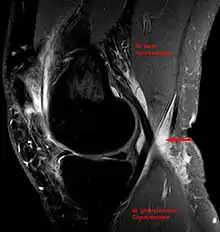

کیست بیکر (به انگلیسی: Baker's cyst) بیرون زدگی غشاء سینوویال در زانو است.بدین معنا که غشای سینوویال به سمت عقب و همچنین پایین زانو امتداد می یابد.چنین وضعیتی در عقب مفصل زانو منجربه افزایش مایع در غشای فتق یافته می گردد.گاهی این حالت به علت افزایش مایع در بورس عقب زانو ایجاد میشود.کیست با اندازههای مختلف در قسمت پشتی داخلی(خلفی داخلی)زانو دیده میشود که به خصوص در حالت ایستاده آشکارتر است[1].